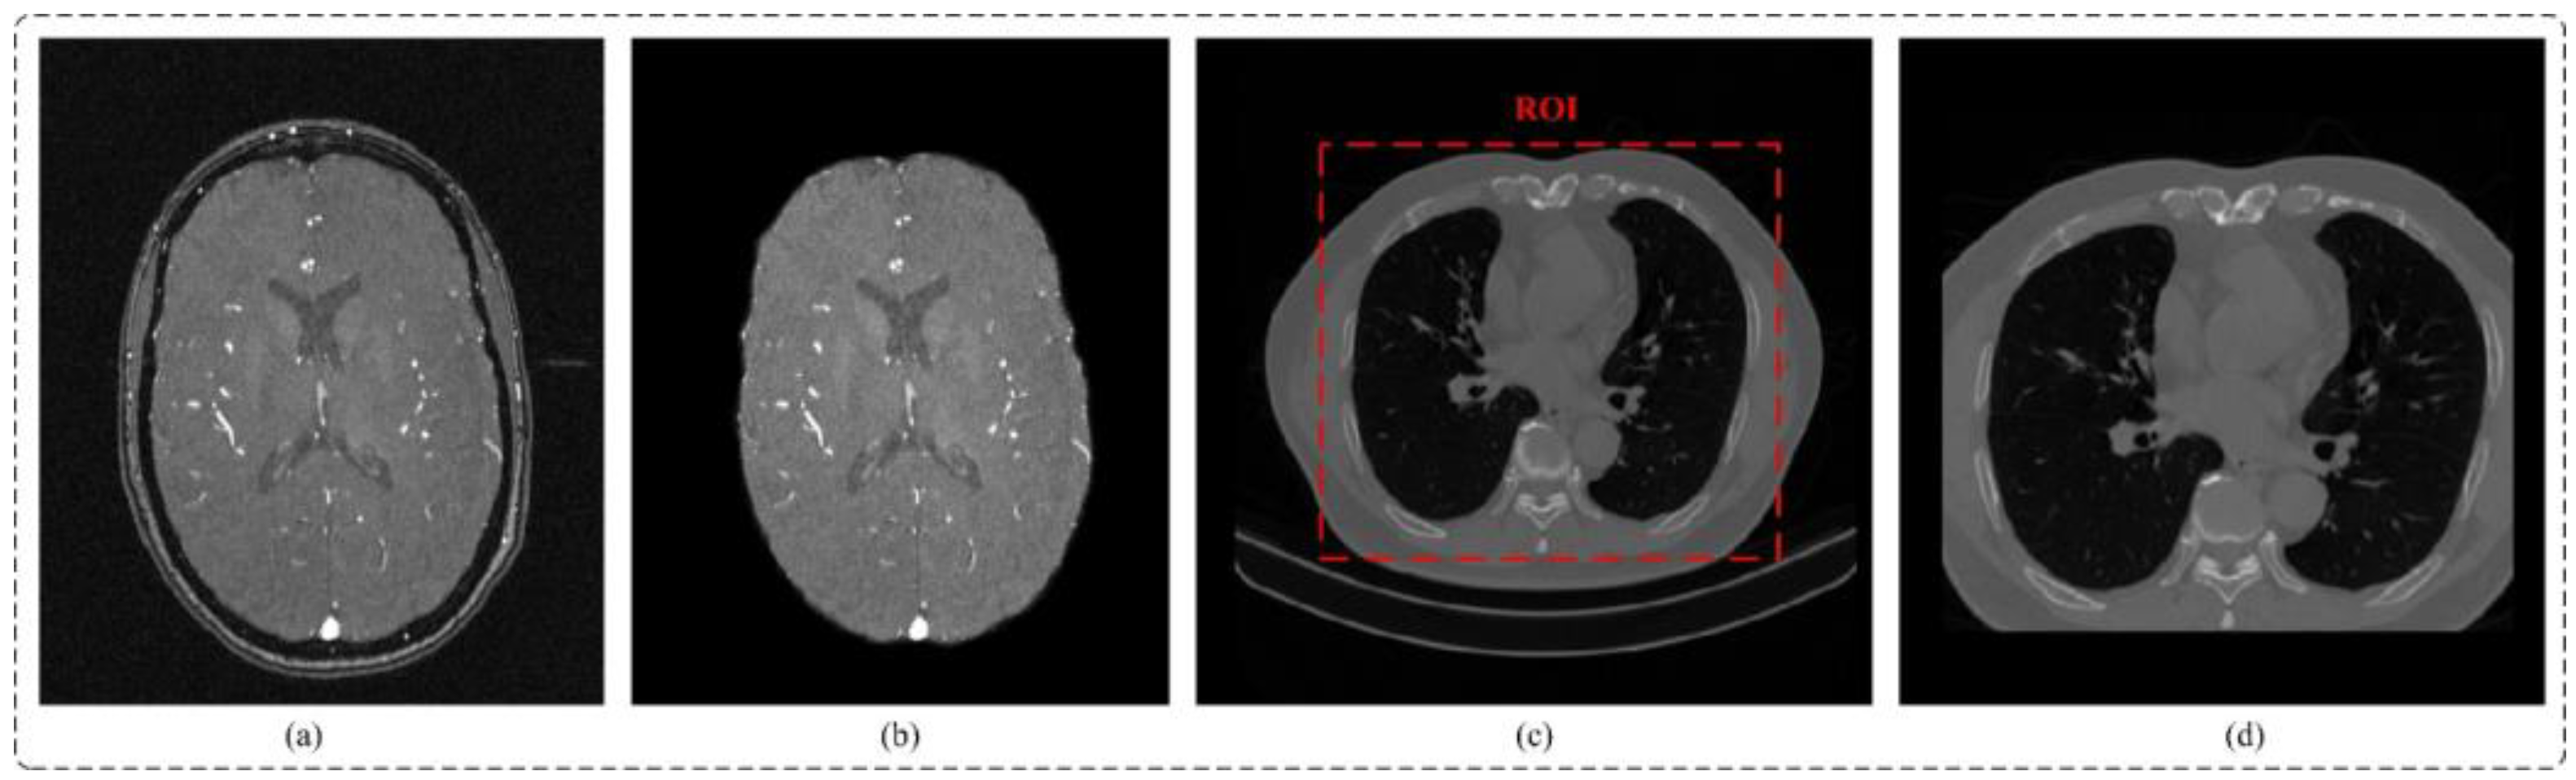

- (a)

- In this paper, a multi-scale feature aggregation method is proposed and validated, which can fully extract and fuse the cerebrovascular and airway features with different thicknesses at different scales. The proposed method effectively solves the problem of differences in feature expression at the same scale, thus improving the segmentation accuracy.

- (b)

- Our paper introduces a novel reverse attention module combined with sparse convolution to guide the network effectively. By leveraging reverse attention mechanisms, this module enhances foreground detection by emphasizing the background and excluding areas of prediction. Moreover, it allocates reverse attention weights to extracted features, thereby improving the representation of micro-airways, micro-vessels, and image edges. The utilization of sparse convolution further improves overall feature representation and segmentation accuracy.

- (c)

- Through extensive experimental validation, we investigate the impact of sliding window sequencing and input image dimensions on the segmentation of tubular structures, including cerebral blood vessels and airways. The insights gained from this study contribute to the advancement of artificial intelligence techniques in medical image analysis, specifically focusing on enhancing the segmentation of tubular structures.